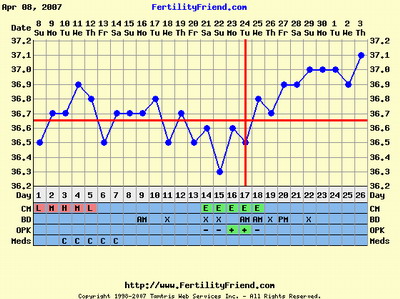

A peteérés megfigyelésére a hőmérőzés jó megoldás, illetve a hüvelyi nyák figyelése, ami félidő táján - tehát peteéréskor - tojásfehérje-szerüvé válik, ez jelzi a közelgő peteérést. A módszert Billings-módszernek hívják, utána tudsz nézni a neten.

Van még olyan hogy LH teszt, ami szintén a peteérést hivatott jelezni, de van már rá több példa is - igaz Lafika ?